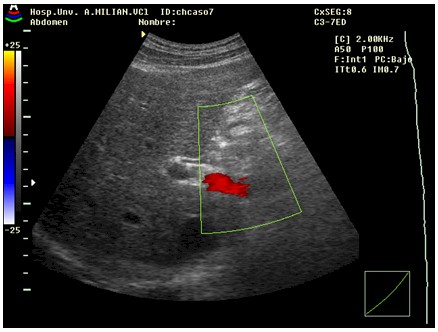

Se le realizó una ecografía abdominal, un Doppler portal (Figura 1.1y 1.2), y medición de la resistencia arterial intrarrenal (Figura 1.3 y 1.4).Todos los estudios ultrasonográficos se realizaron en escala de grises y de Doppler color y espectral con equipo SONOACE 8800 de la firma MEDISON con transductores de 3,5 y 5 MHZ. En el examen portal se registró la permeabilidad del tronco de la porta y sus ramas principales, la dirección del flujo, así como las velocidades medias a nivel de la porta y la esplénica.

Ecografía abdominal: Hígado que rebasa 2cm el reborde costal, con aumento difuso de la ecogenicidad, superficie micronodular, esplenomegalia. Calibre de la porta: 1,6cm.En el estudio doppler del eje esplenoportal, se detecta la presencia de flujo a nivel de la porta, hepatofugal (Figura 1.1) La velocidad media a nivel de la porta fue de 7,5cm/seg, con tendencia al aplanamiento de la curva de flujo nivel de la misma(Figura 1.2). Un calibre portal mayor de 12-13 mm (según los estudios) permite establecer el diagnóstico de cirrosis con especificidad superior al 90 % y sensibilidad por encima del 50 %.La disminución de la velocidad de flujo portal, el aplanamiento de la curva de flujo, y la presencia de un flujo hepatofugal son hallazgos habituales en casos de hipertensión portal.